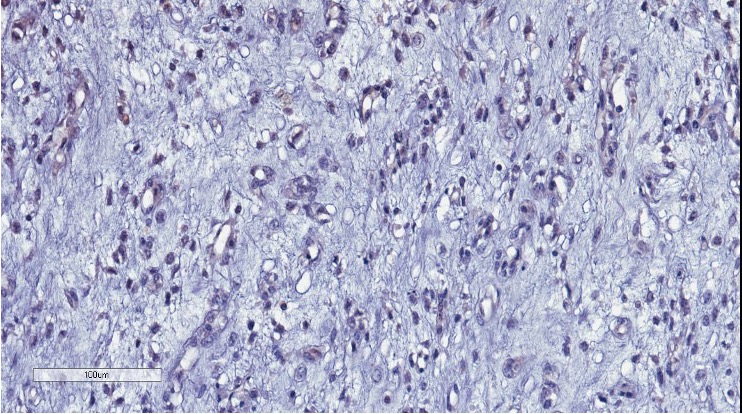

Cells of a type of sarcoma called myxoid liposarcoma. Credit: Garvan